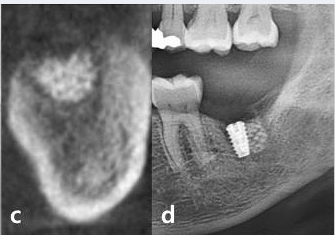

Case photos provided by: Polycaprolactone Impregnated 3D Printed Nanohydroxyapatite for Sinus Augmentation: A Randomized Controlled Trial

Characteristics of 3DPHA‐PCL. (a) Clinical view of 3DPHA‐PCL particles. (b, c) Scanning electron microscopic images of the particle.